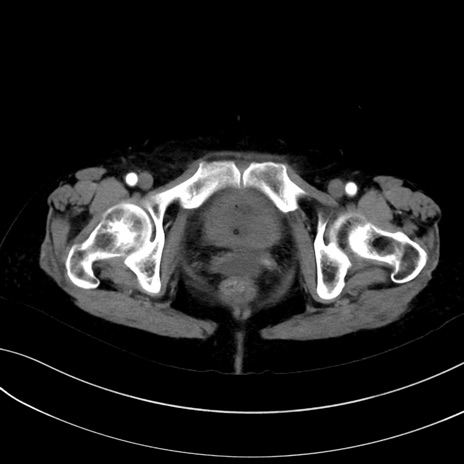

症例13 CT(横断像)1日半後